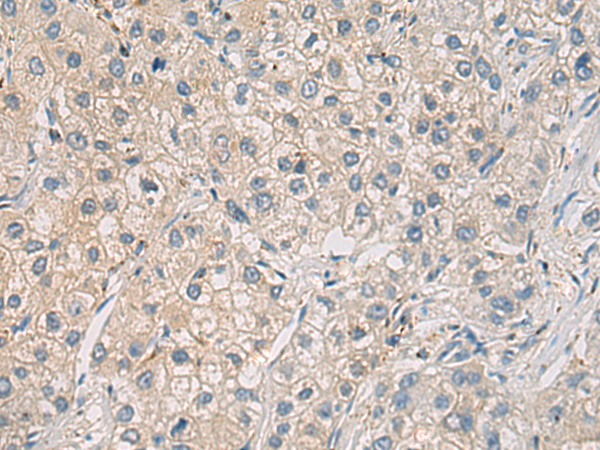

分类: 科研抗体货号: P12899别名: IGI; IGVPB; VPREB; CD179a应用: IHC反应种属: Human